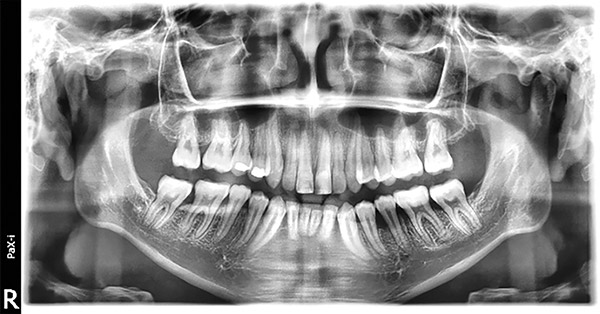

En la radiografía panorámica se observan 28 dientes permanentes presentes con el 35 en posición hacia mesial (Figura 8).

Figura 8. Radiografía panorámica.

En la radiografía panorámica, se muestra 28 dientes permanentes el correcto paralelismo radicular, la verticalización de 35 (Figura 24).

Figura 24. Rx. panorámica.